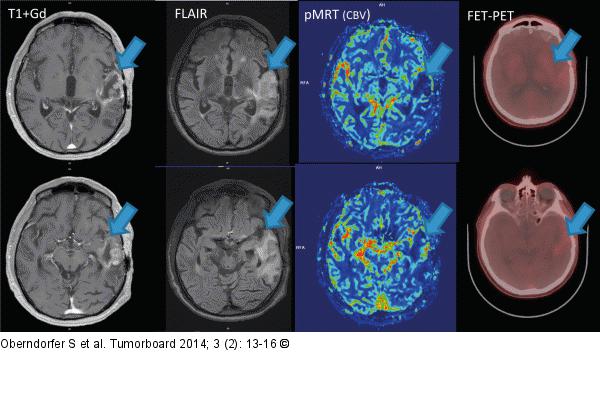

Abbildung 4: Glioblastom Follow-up-Imaging vom Mai 2014: MRT + KM, MRT-FLAIR und pMRT, sowie FET-PET zeigen nach wie vor keine eindeutigen Hinweise auf Tumoraktivität. Vergleiche Abb. 2 und 3 (Tumorbereich mit Pfeil markiert) |

Follow-up-Imaging vom Mai 2014: MRT + KM, MRT-FLAIR und pMRT, sowie FET-PET zeigen nach wie vor keine eindeutigen Hinweise auf Tumoraktivität. Vergleiche Abb. 2 und 3 (Tumorbereich mit Pfeil markiert) |